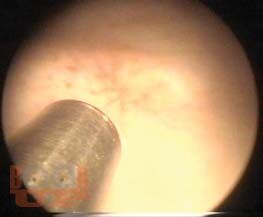

В пособии, наряду с традиционными, представлен универсальный для диагностики заболеваний нижних мочевых путей метод — кроссполяризационная оптическая когерентная томография. На основе патогенетического подхода освещены основные принципы лечения цистита.